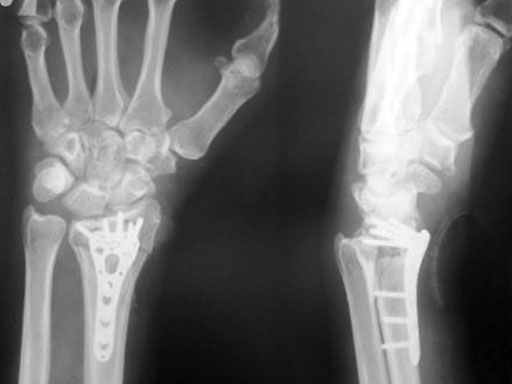

Fig 2a-b Post-op immediate

Fig 3a-b Post-op 3 months